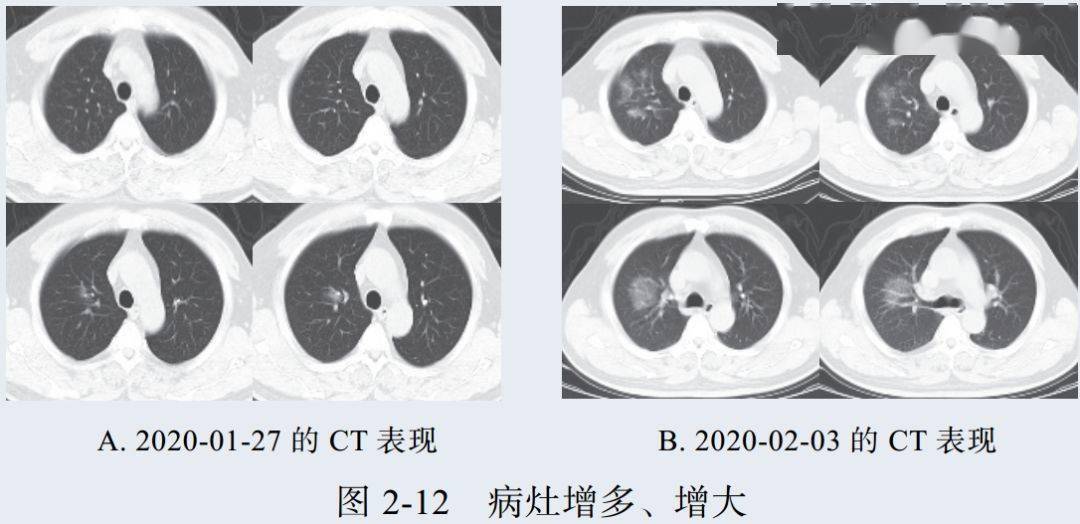

新冠肺炎大多数病例进展迅速,复查 CT 影像发生明显变化

表现为病灶数目明显增多,范围明显扩大,密度增高,病灶分布由外周向中央推进

根据既往 SARS 病理学机制,提示为肺泡腔内聚集大量细胞渗出液、间质内血管扩张渗出;肺泡连通起来形成融合态势(图 2-11)

图 2-11 病灶数目增多、范围扩大 (A-D)